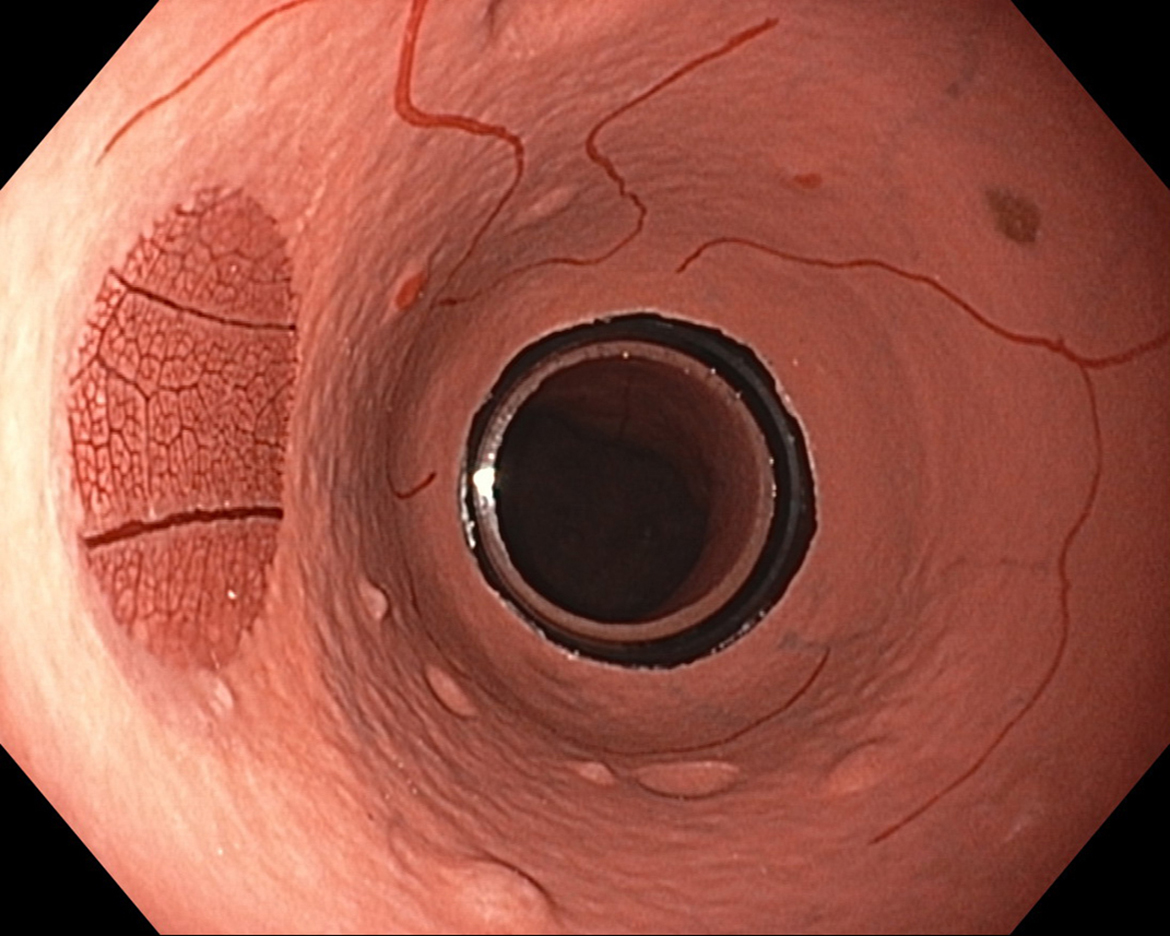

EVIS LUCERA ELITE × GIF-1200N 、EVIS X1 × GIF-H190N 什器比較画像

面順次式、同時式で色味の違いはありますが、どちらもハイビジョン画質にて観察可能です。

EVIS LUCERA ELITE×GIF-1200N